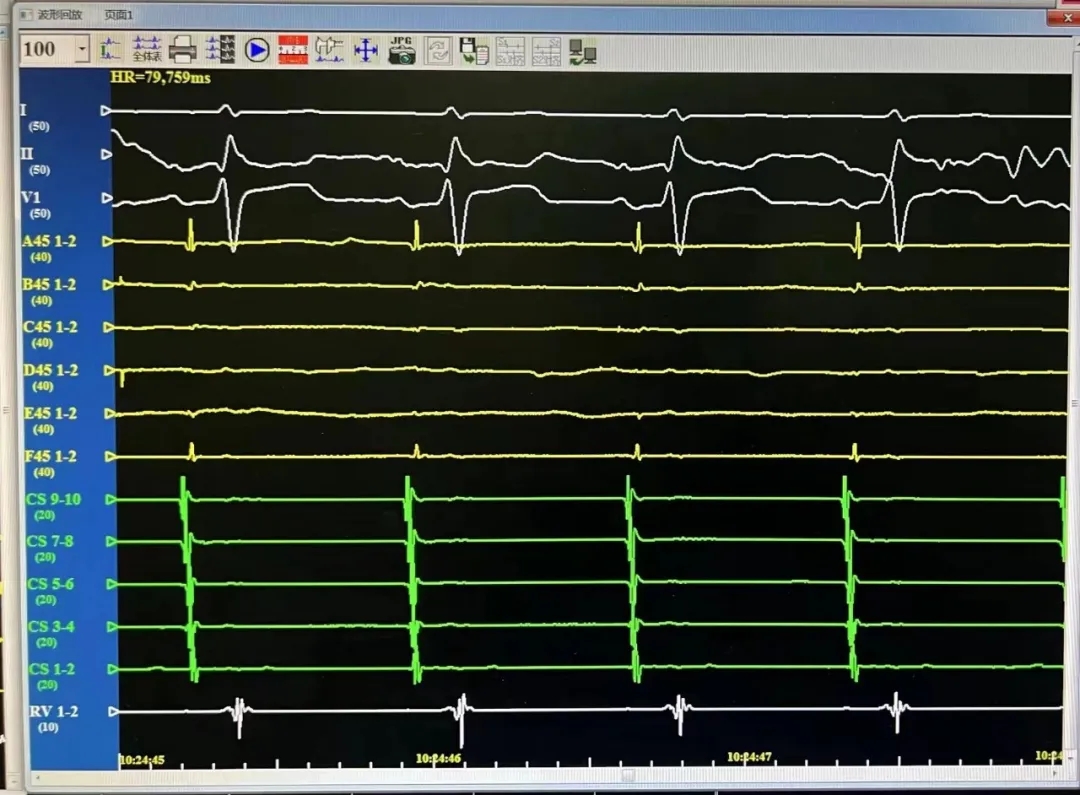

LIPV,消融前后电位。消融后电位即刻消失。

RSPV,消融前后电位。消融后电位即刻消失。